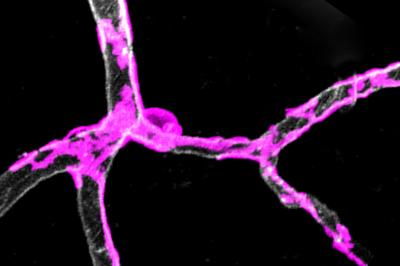

Abnormality with special cells that wrap around blood vessels in the brain leads to neuron deterioration, possibly affecting the development of Alzheimer's disease, a USC-led study reveals.

"Gatekeeper cells" called pericytes surround blood vessels. They contract and dilate to control blood flow to active parts of the brain.

Pericyte dysfunction suffocates the brain, leading to metabolic stress, accelerated neuronal damage and neuron loss, said Zlokovic, holder of the Mary Hayley and Selim Zilkha Chair in Alzheimer's Disease Research.

To test the theory, researchers stimulated the hind limb of young mice deficient in gatekeeper cells and monitored the global and individual responses of brain capillaries, the smallest blood vessels in the brain. The global cerebral blood flow response to an electric stimulus was reduced by about 30 percent compared to normal mice, denoting a weakened system.

Relative to the control group, the capillaries of pericyte-deficient mice took 6.5 seconds longer to dilate. Slower capillary widening and a slower flow of red blood cells carrying oxygen through capillaries means it takes longer for the brain to get its fuel.